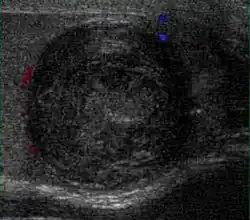

Primary leukemia of the testis is rare. However, due to the presence of blood-testis barrier, chemotherapeutic agents are unable to reach the testis, hence in boys with acute lymphoblastic leukemia, testicular involvement is reported in 5% to 10% of patients, with the majority found during clinical remission. The sonographic appearance of leukemia of the testis can be quite varied, as the tumors may be unilateral or bilateral, diffuse or focal, hypoechoic or hyperechoic. These findings are usually indistinguishable from that of the lymphoma [Fig. 9].

Fig. 9. Leukemia. Diffuse hypoechoic infiltrative lesions are seen involving the whole testis, indistinguishable from that of the lymphoma.